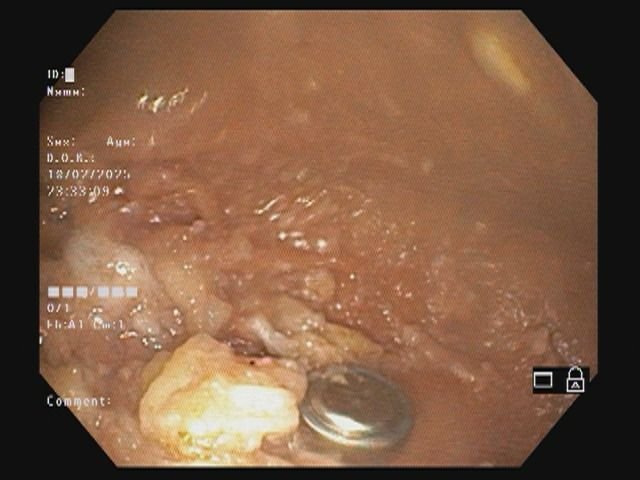

डॉ.अग्रवाल ने बताया कि प्रसिद्ध गैस्ट्रोलॉजिस्ट डॉ.निखिल गांधी से बच्चे की स्थित व एक्सरे में दिखाई देने वाले बटन बैटरी के के रूप में बताया। डॉ. गांधी ने कोठारी अस्पताल में एंडोस्कोपिक रूप से बटन बैटरी को सफलतापूर्वक निकाल दिया। डॉ.निखिल गांधी और उनकी टीम को जीवन रक्षक प्रक्रिया अपनाते हुए निस्वार्थ प्रयासों तथा डॉ.गांधी के समर्पण और विशेषज्ञता लिए उन्होंने तथा बच्चे, उसके अभिभावक ने हृदय से धन्यवाद दिया।